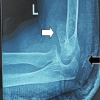

X-rays revealed cystic expansion and cortical thinning [3] of the proximal phalanges with lytic lesions (Fig. 2). Computed tomography imaging confirmed cortical destruction and periosteal reaction (Fig. 3).

Figure 2: X-ray B/L hands showing involvement of phalanx.